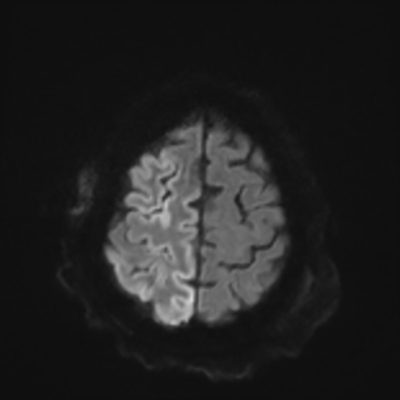

You come back the next day and see how things are going. The patient's electrographic record has shown a moderate encephalopathy (diffuse slowing, disorganization) with frequent right posterior quadrant delta slowing. Based on this result, and an adequately improved clinical examination, you give the okay to proceed with obtaining an MRI of his brain. This is shown below.

MRI brain (DWI)